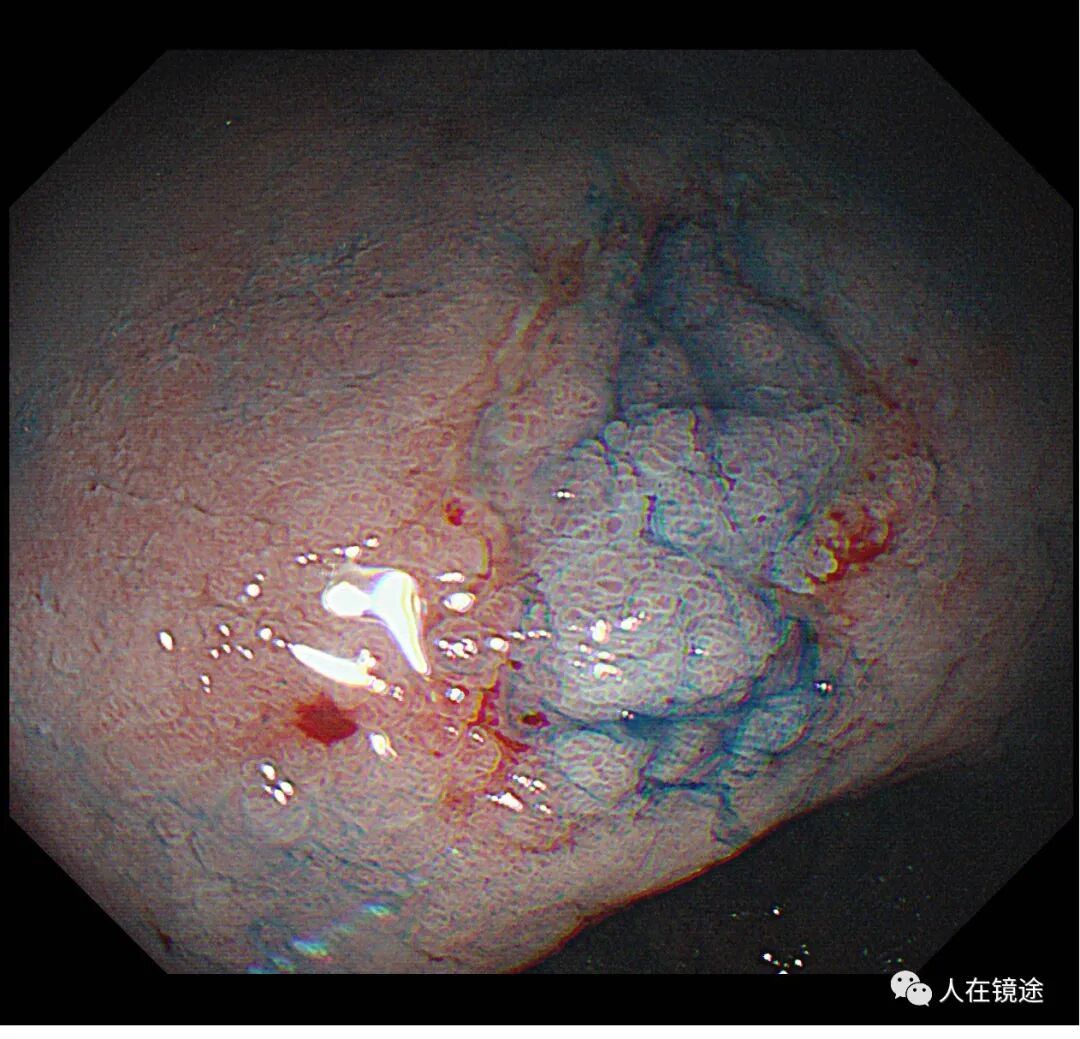

靛胭脂+醋酸示:病变边界清楚,约0.8*1.2cm大小,表面粘膜高低不平,微结构紊乱伴自发性出血,中央见腺管密集不规则,

NBI+靛胭脂+醋酸+近焦示:病变边界清楚,约0.8*1.2cm大小中央见腺管密集不规则伴自发性出血。